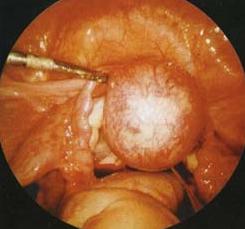

腹腔鏡觀察宮角妊娠宮角妊娠是指受精卵種植在子宮的角部。宮角妊娠與輸卵管間質部妊娠不同,宮角妊娠患者雖有嚴重腹痛,但大多數病例都可自然分娩,這一點與間質部妊娠截然不同,後者一定要手術治療。其受精卵附著在輸卵管口近宮腔側,胚胎向宮腔側發育生長而不是向間質部發育。

宮角妊娠孕婦宮角妊娠與輸卵管間質部妊娠的鑑別輸卵管間質部位於宮角,是輸卵管通向子宮的交接處,有子宮肌組織包繞,全長約2.0cm,受精卵種植在該部,即形成間質部妊娠。因孕卵在宮角輸卵管開口處輸卵管側的宮腔外著床、發育,屬異位妊娠範疇。腹腔鏡檢查或開腹時,可根據圓韌帶位於突出包塊的關係與輸卵管間質部妊娠鑑別。若圓韌帶位於突出包塊的外側為子宮角妊娠,如圓韌帶位於突出包塊內側為輸卵管間質部妊娠。

腹腔鏡觀察宮角妊娠1.治癒臨床症狀消失、血β一HCG降至正常、盆腔包塊縮小或消失。